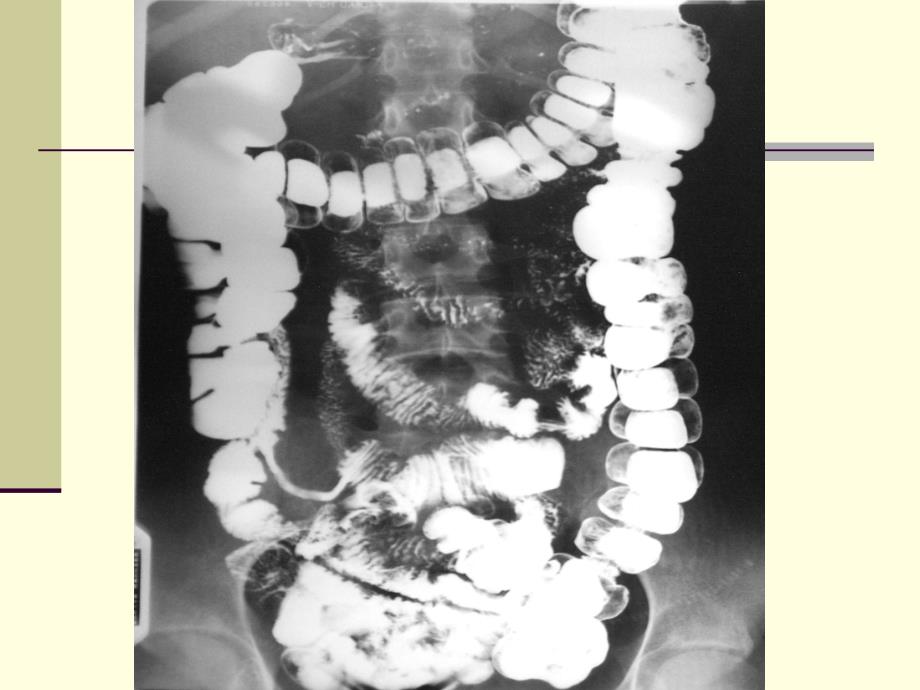

1、大肠疾病的影像学诊断Imageological Diagnosis of the Large Intestine大肠癌大肠癌(carcinoma of the large intestine)=流行病学:流行病学:=病因学:病因学:内因内因 外因外因=病理学:增生病理学:增生(54.2%)溃疡溃疡(28.1%)浸润浸润=组织学:腺癌组织学:腺癌 黏液癌黏液癌 印戒细胞印戒细胞 未分化未分化=临床表现:梗阻临床表现:梗阻 血便血便=诊断:影像诊断:影像 内镜内镜进行期大肠癌进行期大肠癌发发 生:生:1.腺瘤恶变的基础上,即腺瘤内癌腺瘤恶变的基础上,即腺瘤内癌 2.粘膜上皮癌变而来粘膜上皮癌变而来

2、 3.溃疡性结肠炎癌变(溃疡性结肠炎癌变(1/4)部部 位:直肠位:直肠50%,乙状结肠,乙状结肠25%,直肠,直肠+乙状结肠乙状结肠3/4病病 理:增生型、溃疡型、浸润型理:增生型、溃疡型、浸润型组织学:分化型占组织学:分化型占80%-90%,未分化型占比例小,与胃癌,未分化型占比例小,与胃癌 相反相反临临 床:腹部肿块、便血、腹泻、便秘、便细、里急后重床:腹部肿块、便血、腹泻、便秘、便细、里急后重诊诊 断:结肠造影、内镜断:结肠造影、内镜 进展期大肠癌进展期大肠癌主要主要X线表现线表现 增生型:增生型:=充盈缺损自肠壁侧向腔内突出,充盈缺损自肠壁侧向腔内突出,表面可有龛影表面可有龛影=肠管

3、多为偏侧性狭窄肠管多为偏侧性狭窄=局部肠壁僵硬、黏膜破坏、蠕动消失局部肠壁僵硬、黏膜破坏、蠕动消失进展期大肠癌进展期大肠癌主要主要X线表现线表现溃疡型:溃疡型:=大而不规则龛影位于肠腔轮廓之内大而不规则龛影位于肠腔轮廓之内=周边有多个尖角及宽窄不一透亮带周边有多个尖角及宽窄不一透亮带(环堤环堤)=局部肠壁僵硬、肠袋消失、黏膜破坏局部肠壁僵硬、肠袋消失、黏膜破坏进展期大肠癌进展期大肠癌主要主要X线表现线表现浸润型:浸润型:=多为局限性环形不规则狭窄,分界多为局限性环形不规则狭窄,分界 清楚,近端肠管扩张清楚,近端肠管扩张=黏膜破坏,呈结节状,肠壁僵硬、肠袋黏膜破坏,呈结节状,肠壁僵硬、肠袋消失消失大肠癌大肠癌CT表现表现=腔内肿块腔内肿块 光滑或绒毛状边缘光滑或绒毛状边缘=肠壁增厚肠壁增厚 局限性或环形局限性或环形 2cm范围范围=弥浸性钙化或坏死低密度影弥浸性钙化或坏死低密度影=靶形影像靶形影像 肿瘤伴套叠肿瘤伴套叠=周围脂肪层模糊消失,周围脂肪层模糊消失,LN肿大,肝肿大,肝M